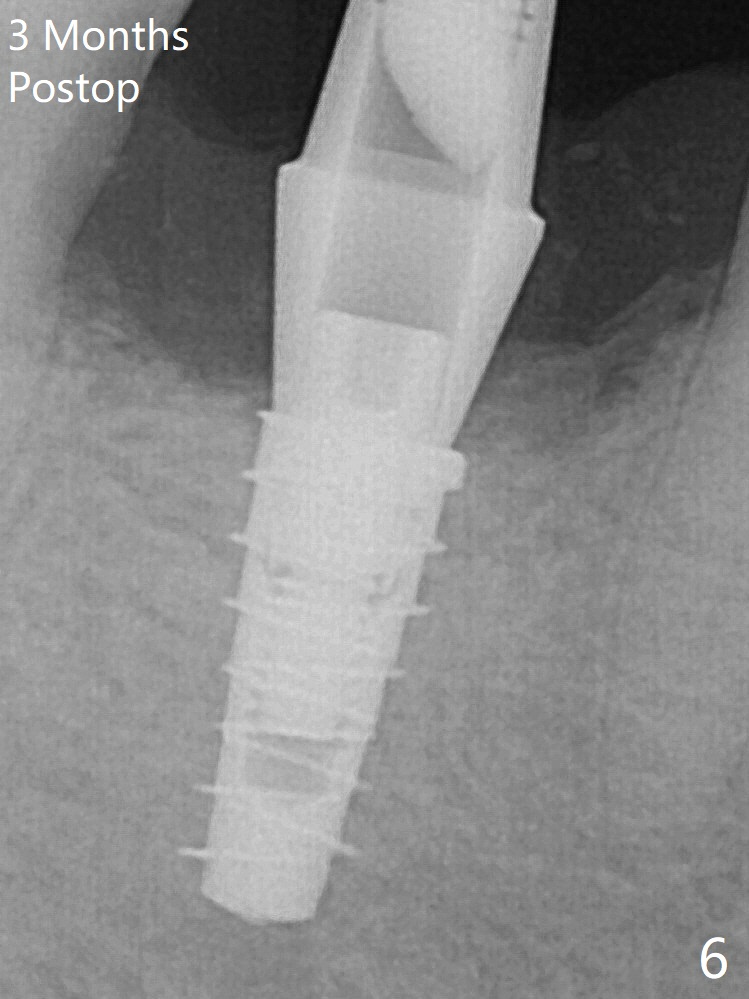

For safety, a 4x9 mm IBS implant is placed with insertion torque 40 Ncm; a 5x5.7(4) mm abutment is immediately placed for an immediate provisional to cover the large socket and keep Vera graft in place (Fig.4 *). Yellow dashed line: apical osteotomy; red dashed line: Mental Loop. Impression is taken nearly 3 months postop (Fig.6).